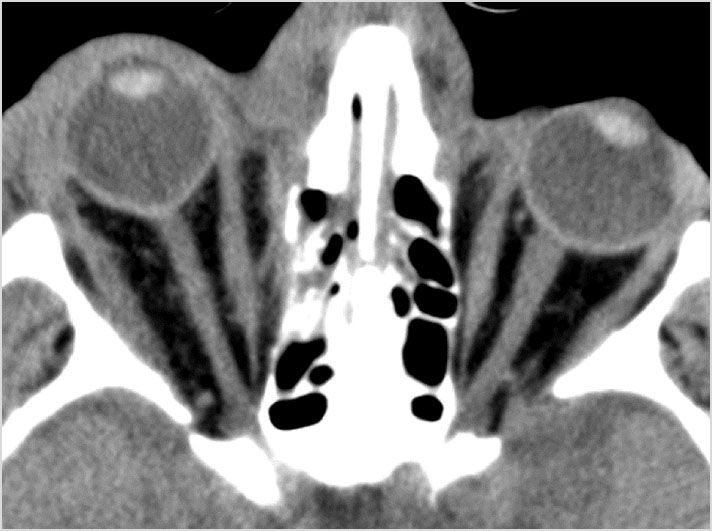

Orbits and Orbital Zygomatic Complex

Eyes

Proptosis is present.

The optic nerve has a stretched appearance.

The posterior aspect of the globe is tented.

There are signs of a decompressed globe.

The lens is in abnormal position on either side.

There is evident general optic sheath swelling or swelling at the junction of the globe and sheath to suggest an optic sheath hematoma.